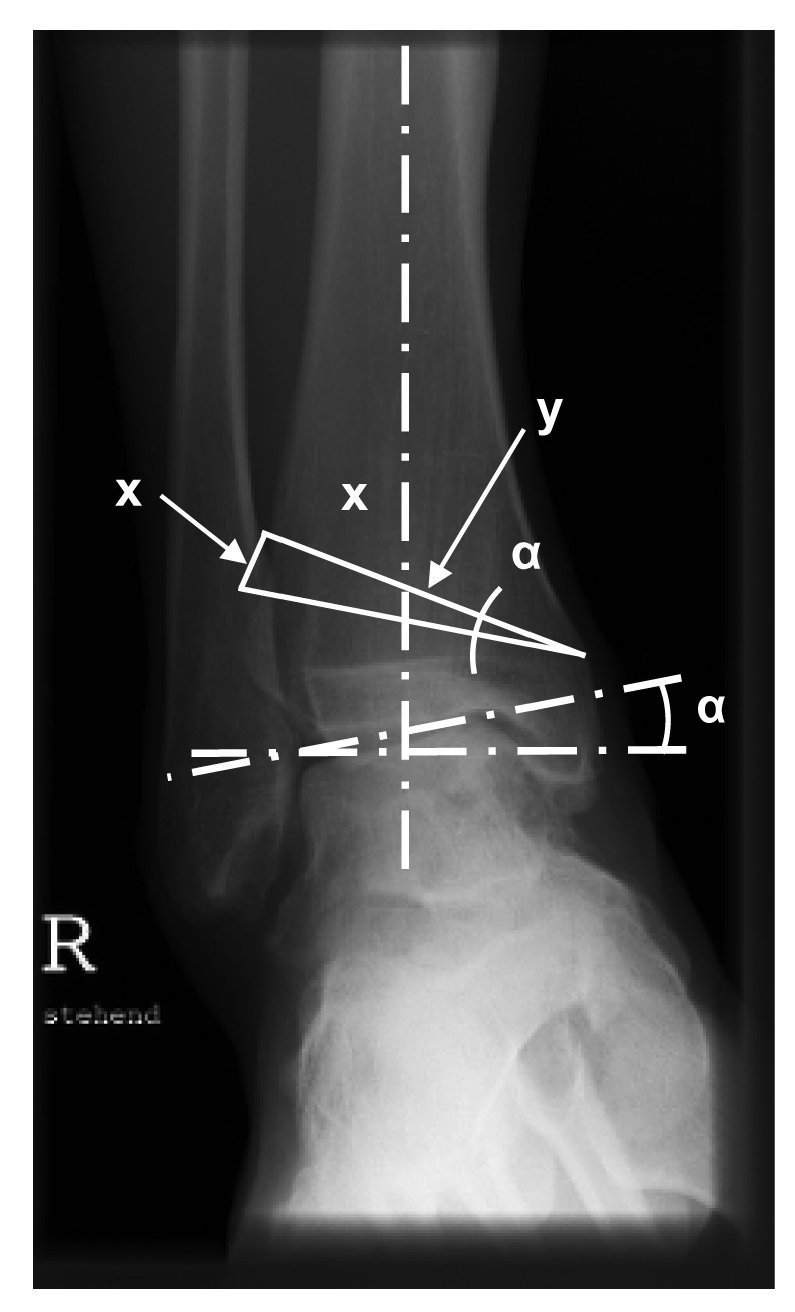

Figura 1. Planificación de la osteotomía. La siguiente operación permite calcular aproximadamente la altura de la base de la cuña que debe extraerse de la tibia: x = y x tan a. En la osteotomía, por tanto, se realizará probablemente una corrección de 1º para una resección de 1 mm (menor en correcciones más pequeñas).